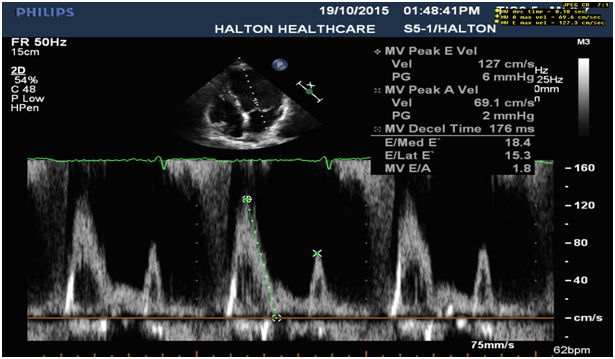

6. Systolic reverse blood flow in pulmonary vein (Figure 5) and dominant E wave in MV inflow with elevated LA pressure and high LV diastolic pressure (Figure 6).

Figure 6: E- wave dominant mitral inflow (E>1.2m/s) with signs of elevated LA and high LV diastolic pressure (L wave).

E-wave dominant mitral inflow (E›1.2 m/s), enlarged LV and LA

E-wave 1.27 m/s, normal LV size with increased LV diastolic pressure, and moderately enlarged LA volume with increased LA pressure